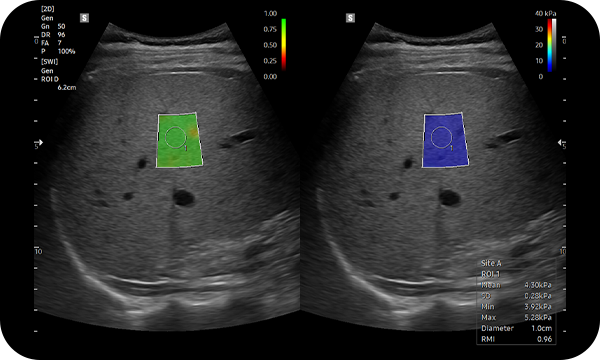

S-Shearwave Imaging™ permite una evaluación no invasiva de la rigidez del tejido/lesiones del hígado. Las funciones de elastograma con códigos de colores, las mediciones cuantitativas, la opción de pantalla simple o doble y el ADI definido por el usuario son muy útiles para el diagnóstico preciso de las enfermedades hepáticas.